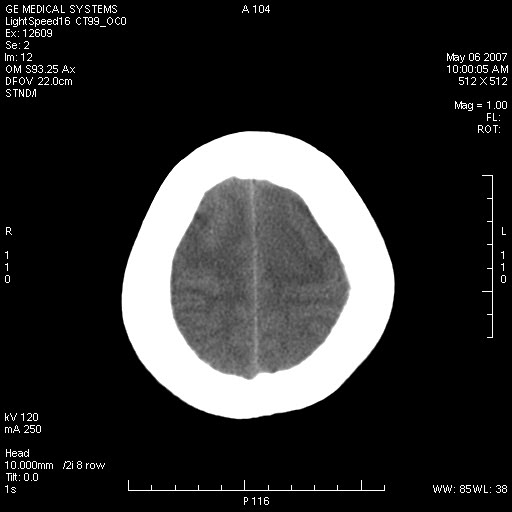

女,60岁,头痛6~7天。

右颞叶巨大高低混杂密度肿块,病灶内可见多发条块状钙化影,占位效应明显,中线结构显著左偏,肿块周围水肿明显,临近颅骨吸收变薄,边缘光整,考虑1少枝胶质瘤2脑膜瘤3转移瘤4室管膜瘤5淋巴瘤6三叉神经瘤(多多益善)合并镰下疝

右颞叶分叶状稍高密度灶,占位效应明显,外周见水肿带,其内见点条样高密度钙化灶,临近颅骨变薄,考虑:脑膜瘤,少突胶质瘤。

右颞叶混杂密度,累及右额叶。其内可见条片状钙化及斑片状略高密度,周围少量水肿,右颞骨吸收变薄,中线结构左移。考虑1少突胶质瘤。2脑膜瘤。合并瘤卒中。建议增强扫描。

右额、颞叶巨大高低混杂密度肿块,病灶内可见多发条块状钙化影,占位效应明显,中线结构显著左偏,肿块周围水肿明显,临近颅骨吸收变薄,边缘光整。

考虑:1、少枝胶质瘤;

2、脑膜瘤?

3、镰下疝;

4、建议增强扫描进一步检查。